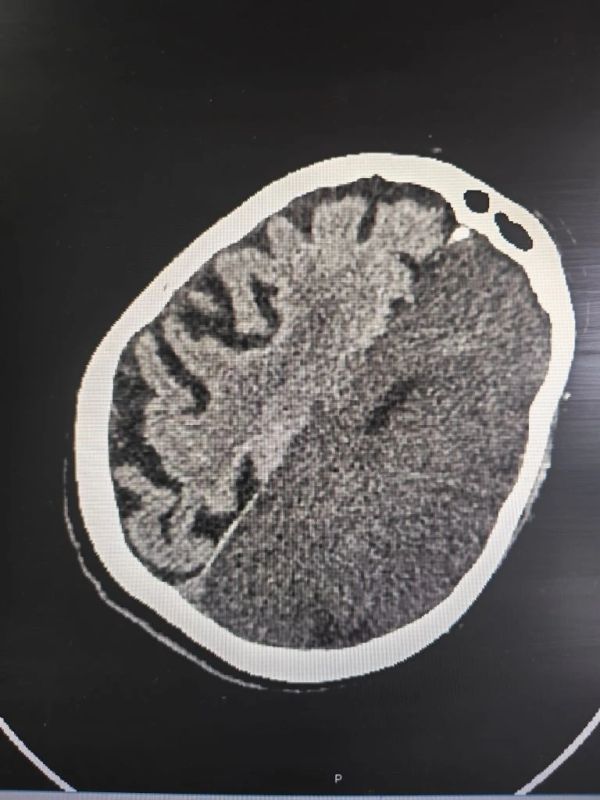

76-летняя пациентка попала в больницу в тяжёлом состоянии, у неё отсутствовали движения с правой стороны тела. Компьютерная томография показала обширный ишемический инсульт, при котором произошло острое нарушение кровообращения и гибель клеток головного мозга. Это один из наиболее опасных видов сосудистой катастрофы.